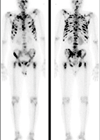

Imaging and radiology

Case 1 What radiological test is this and what does it show? What is the typical radio-nucleotide used for this study, what is its half-life and how is it excreted? Approximately how long does this study take to perform? What...